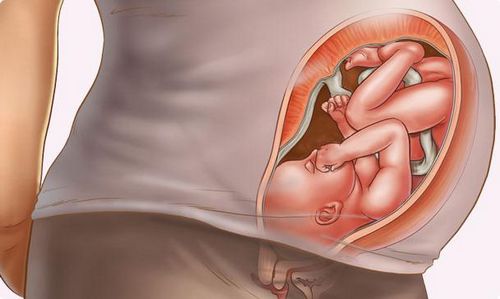

Як розпізнати ворушіння плода при вагітності? Коли починається ворушіння плода при першій вагітності?

Обов'язково потрібно провести порівняння рухової активності ембріона між різними періодами очікування малюка. Також варто сказати, коли починається ворушіння плода при першій вагітності.

У всій медичній літературі дається інформація про те, що перше ворушіння малюка починається приблизно в два місяці його розвитку. Розглянемо докладно, коли можна відчути ворушіння плода при першій вагітності.

На цьому терміні починаються найперші руху крихти. Однак майбутня мама ще не може їх відчути, як би вона не старалася. У цей час дітородний орган знаходиться глибоко в малому тазу. Плід надійно укритий не тільки стінками матки, але і кістками жінки.

Як розпізнати ворушіння плода при першій вагітності на цьому терміні? Єдиним способом зафіксувати рухову активність малюка є ультразвукова діагностика. Під час дослідження лікар оглядає порожнину матки за допомогою спеціального датчика і зазначає, як ембріон рухає ручками та ніжками.